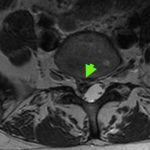

L5S1腰椎間盤突出, 引起神經壓迫和右側嚴重的坐骨神經疼痛,已捱了幾個月!

脊椎微創顯微鏡的神經外科手術

只需要1.5小時和一個2厘米的小傷口,去根治嚴重的神經疼痛

切除突出的椎間盤,為神經根減壓,及移除L5S1椎間盤空間內的退化和鬆散的椎間盤碎片,以防止將來的疾病復發!